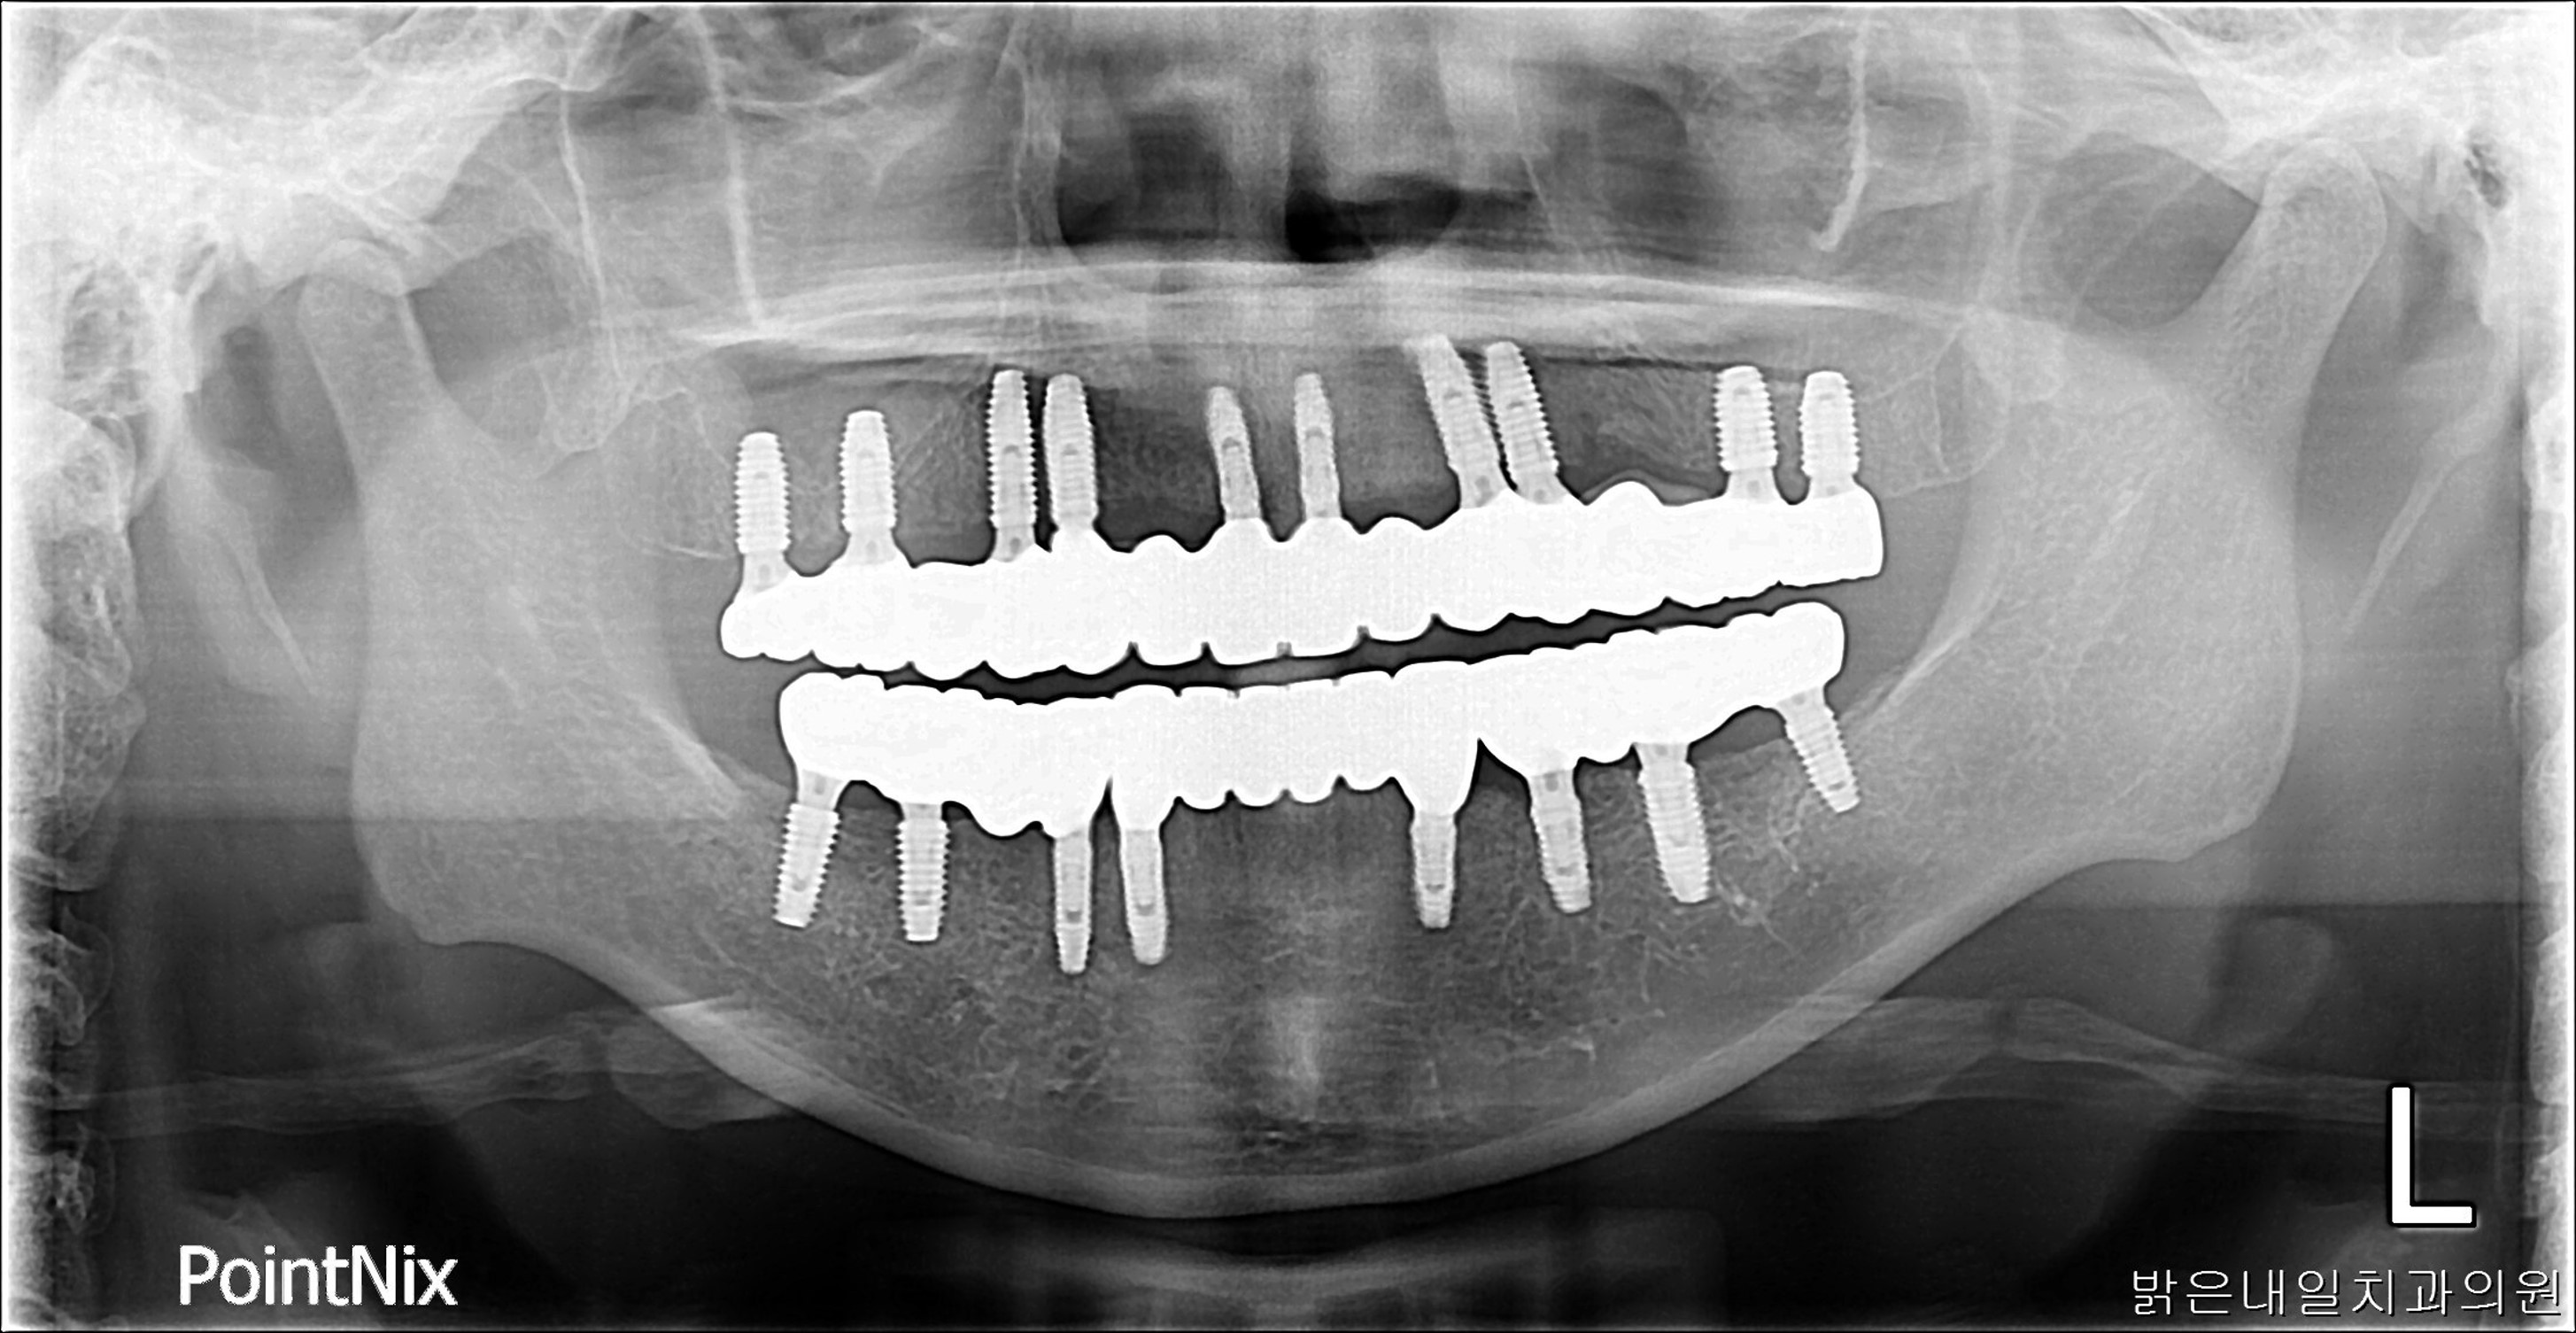

After

남아있는 치아들이 모두 흔들리거나 썪어서 제거 후 전체 임플란트를 시술한 모습입니다.